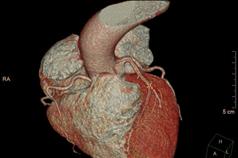

PAÜ Hastaneleri Radyoloji Anabilim Dalı Öğretim Üyesi Doç. Dr. Vefa Çakmak yaptığı açıklama da şunları söyledi: “Pandemi döneminde hayatımıza daha sık giren bilgisayarlı tomografi (BT), günümüzde tanı ve tedavi süreçlerinde hayati önem taşıyan bir görüntüleme yöntemi olarak kullanılmaya devam ediyor. Radyasyon içeren bu teknoloji, pek çok organın ayrıntılı şekilde incelenmesini sağlarken, acil durumlarda hızlı teşhis imkânı sunarak hayat kurtarıcı bir rol üstleniyor. Özellikle kanserin tanı ve takibinde, trafik kazaları, beyin kanamaları, kırıklar ve büyük cerrahiler öncesinde önemli bir yer tutuyor. BT ile kalbi besleyen damarların detaylı şekilde görüntülenmesi mümkün hale geliyor. Halk arasında ‘sanal anjiyo’ olarak bilinen bu yöntemle, kalpte işlem gerektiren damar tıkanıklıkları erkenden saptanabiliyor. Böylece hastalar, gereksiz klasik anjiyo işlemlerinden korunuyor. Aynı anda kalp duvarları, kalp içindeki pıhtı ya da tümör gibi oluşumlar ve ritim bozukluğuna neden olabilecek yapılar da değerlendirilebiliyor. Ayrıca, bu çekimler sırasında düşük dozla akciğer görüntülemesi de yapılarak yapısal akciğer hastalıkları, akciğer kanserleri ve göğüs kafesiyle ilgili kemik problemleri de tespit edilebiliyor. Çekim öncesinde hastanın böbrek fonksiyonlarını korumak amacıyla kreatin ve GFR gibi kan testleri yapılıyor. Hastanın mevcut hastalık öyküsü ve ilaç alerjileri sorgulanıyor. Kaliteli bir görüntü elde edebilmek için kalp atım hızının dakikada 70 civarına düşürülmesi gerekebiliyor; bu durumda nabız düzenleyici ilaçlar kullanılabiliyor. İşlem sırasında hasta monitörize ediliyor, göğüs bölgesindeki metal eşyalar çıkarılıyor ve yaklaşık 10–15 saniyelik nefes tutması isteniyor. Kardiyak BT çekimi 4–10 saniye sürüyor ve görüntülerin değerlendirilip raporlanması genellikle aynı gün içinde tamamlanıyor.”